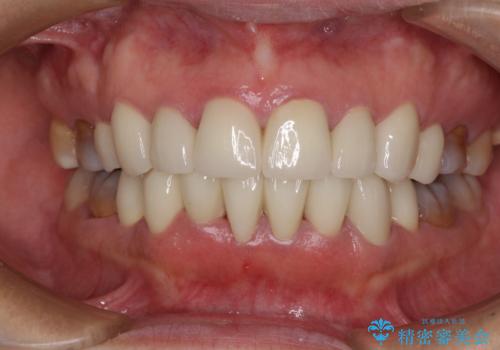

気になる変色歯を仮歯に変え、その後歯列不正を矯正治療で改善し、最後にオールセラミッククラウンにて補綴治療することとしました。

数十年に及んだ歯の変色が改善されたため、大変満足していただきました。